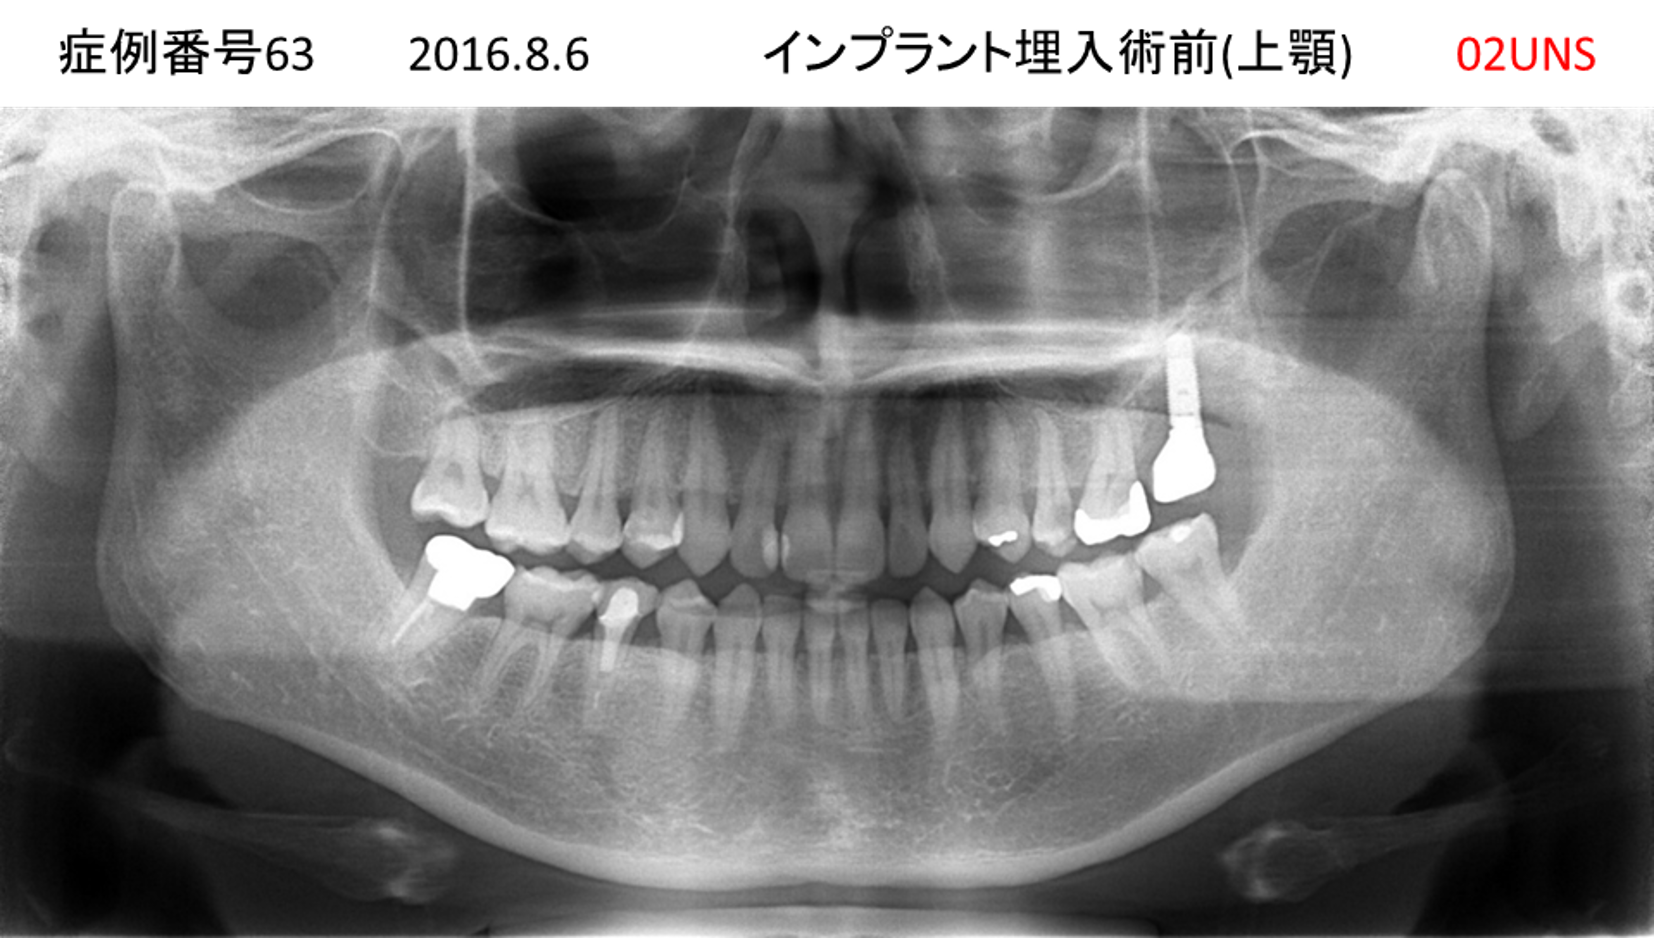

ご飯を美味しく食べたい/人前で笑えるようになりたい患者様のインプラント症例

| 治療名称 |

インプラント |

| 治療費用 |

480万円+税 |

| 治療期間 |

6か月 |

| 患者さんの症状(主訴) |

おいしいご飯が食べられるようになりたい 人前で笑えるようになりたい |

| 治療内容 |

サイナスリフト 抜歯即時インプラント |

| 治療結果 |

何でも食べられるようになった 人前で大口を開けて笑えるようになった |

| 治療の注意点(リスク/副作用) |

インプラントが壊れた場合は再治療が必要 |